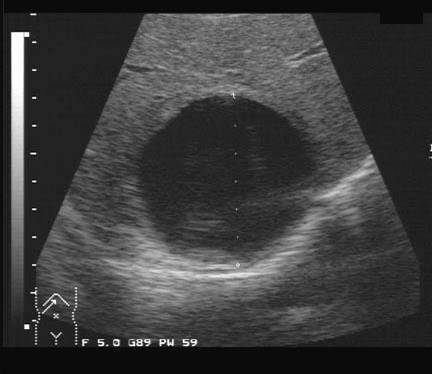

Simple Cyst lesion

SONO

Thin, smooth walled, posterior enhancemnt

increase thru transmision